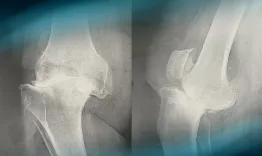

A 68-year-old woman has been suffering from mechanical bilateral knee pain for the past 6 years. The x-rays reveal complex right knee arthritis with ligament deficiency. How would you classify it and how would you manage this condition?

Management of complex knee arthritis with ligament deficiency

Laurent Bedes